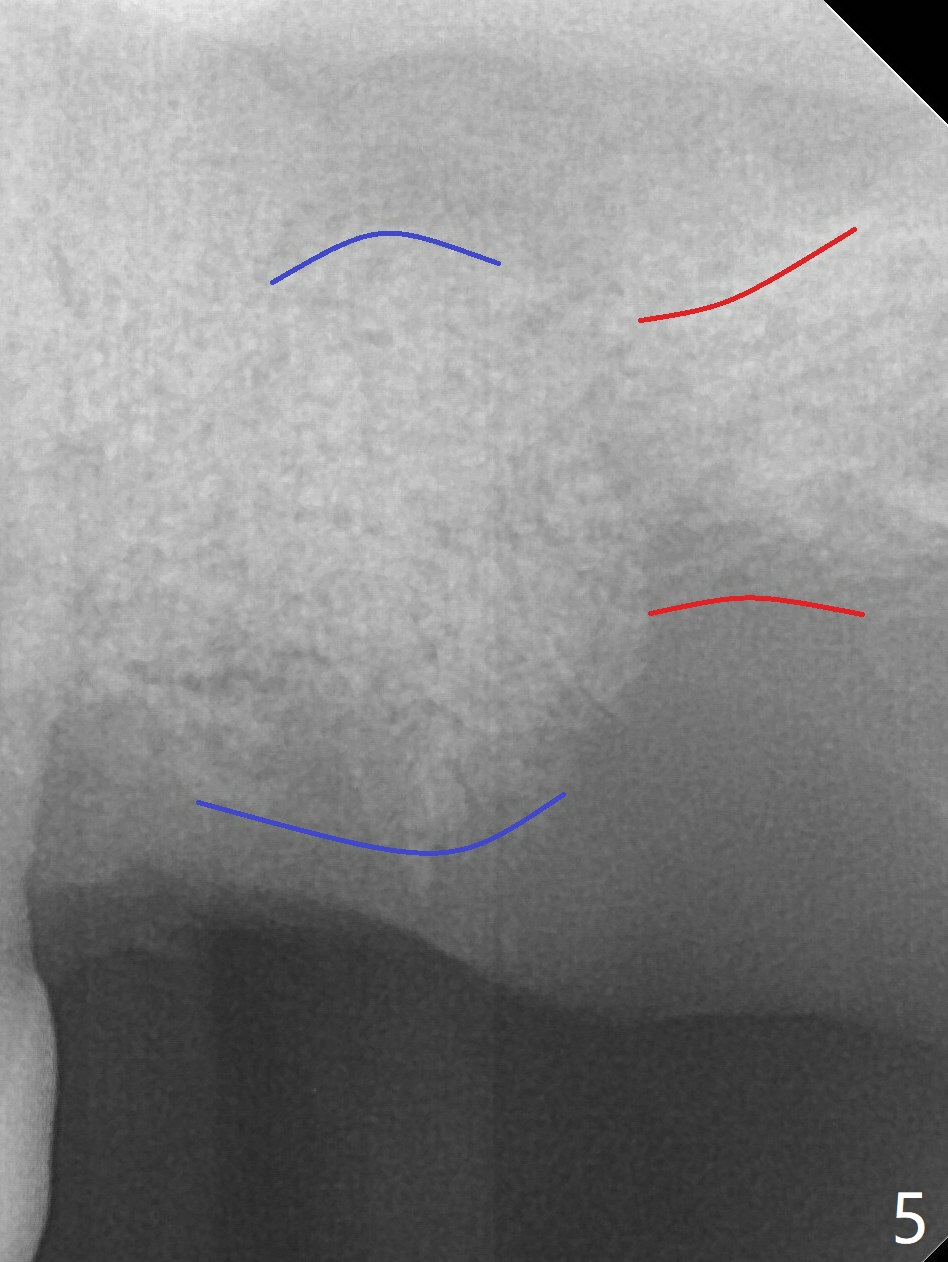

A 54-year-old man returns to clinic 5 months post SRP with chief complaint of UL loose tooth (#15, Fig.1). Since the remaining bone is limited after extraction, it is apparently unsuitable for immediate implant (Fig.2). Socket preservation seems to be able to gain bone height near gingival margin (Fig.3 red line). In fact 1 cc of cortical and cancellous bone mixture is used; after heavy debridement the bone graft is deposited on the distal root surface of the tooth #14 (Fig.4 arrow). The bone increases not only coronally, but also apically (Fig.5 blue lines, as compared to red lines denoting the original bone height). The bone reduces in height 10 months postop (Fig.6). Sinus lift is required for placement of a short implant (Fig.7). Socket preservation does not prevent post-extraction bone loss.